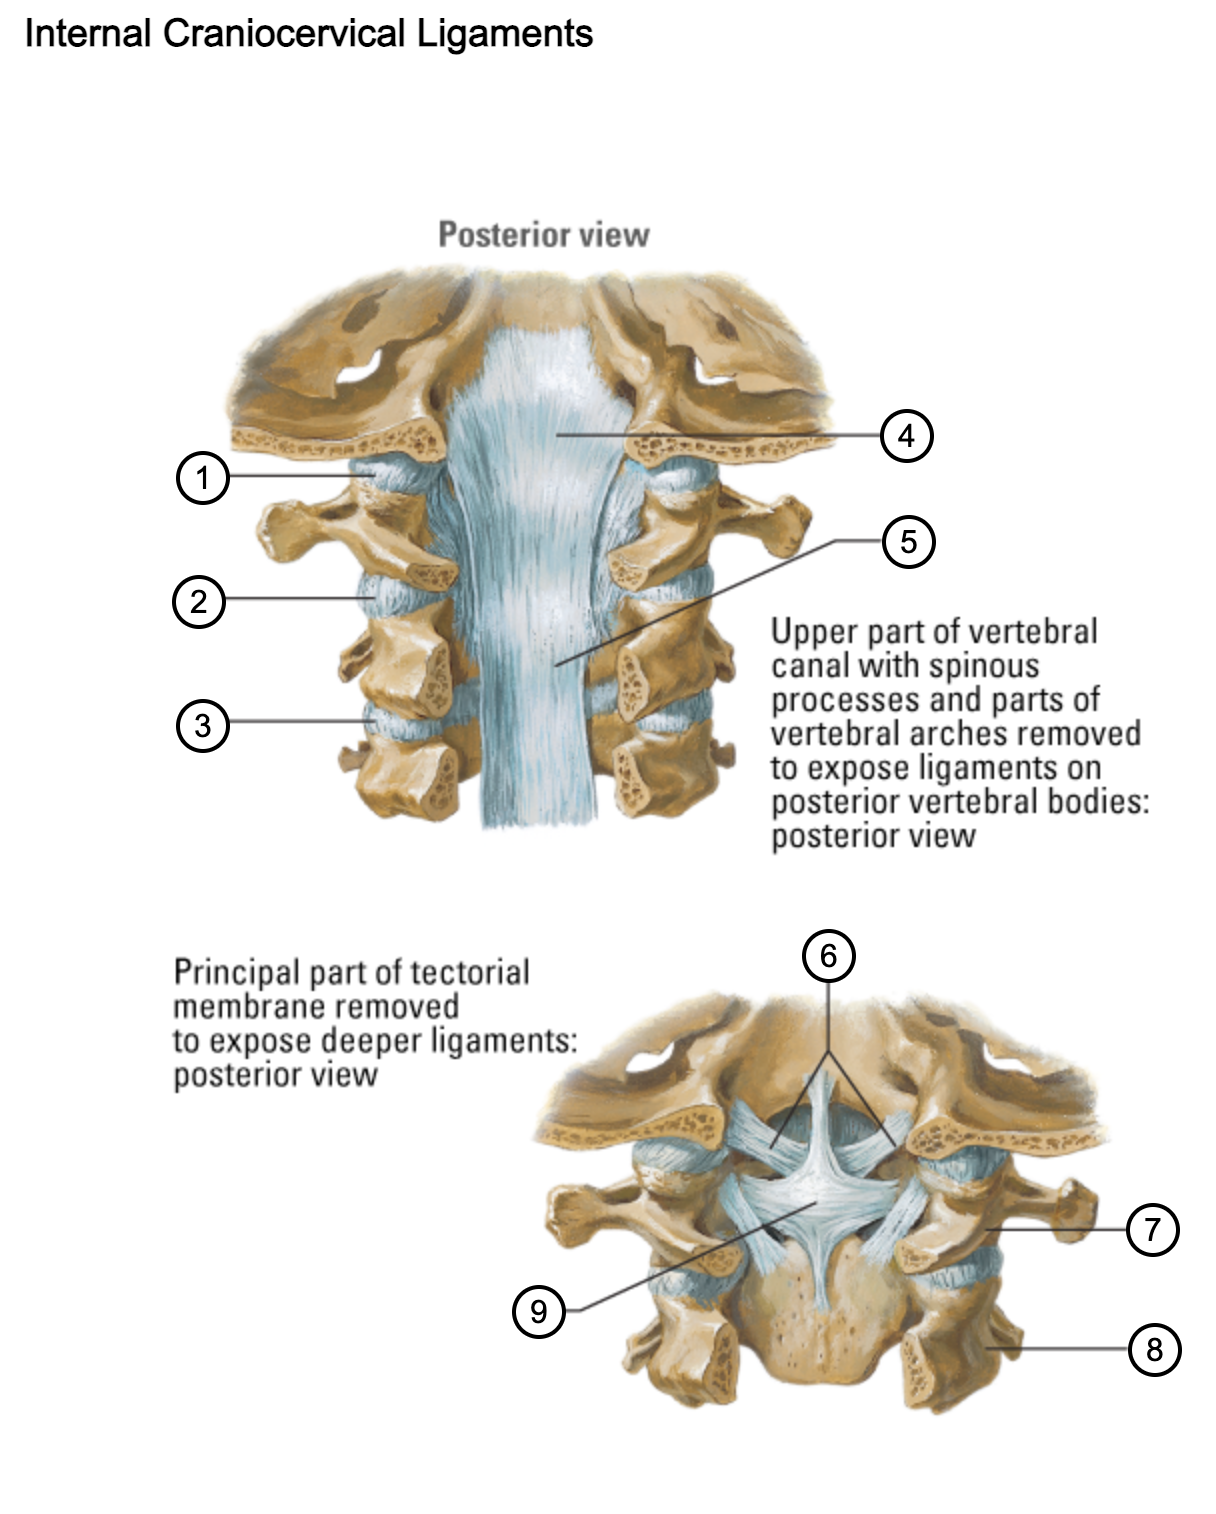

1

capsule of atlantooccipital joint

2

capsule of lateral atlantoaxial joint

3

capsule of zygapophysial joint (between axis and C3 vertebra)

4

tectorial membrane of cervical vertebral column

5

posterior longitudinal ligament

6

alar ligaments

7

atlas (C1)

8

axis (C2)

9

cruciform ligament (superior longitudinal band; transverse ligament of atlas; inferior longitudinal band)